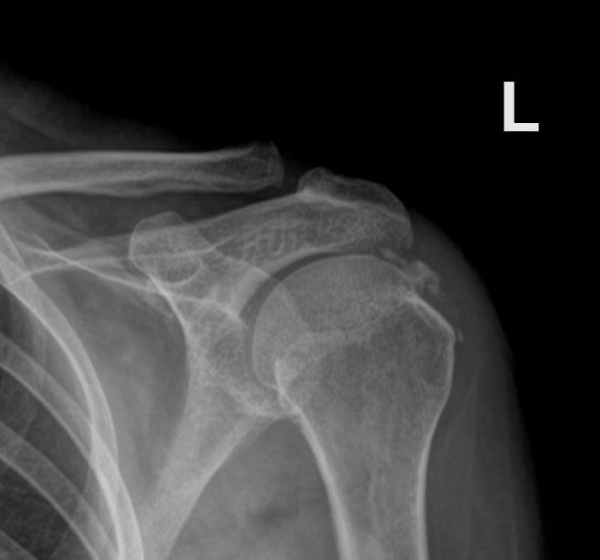

¹æ»ç¼± °Ë»ç :  ÃÊÁø ½Ã ¹æ»ç¼± °Ë»ç¿¡¼­ ¾çÃø ±Ø»ó°Ç°ú °ß°©Çϱٰǿ¡ Å« ¼®È¸°¡ °üÂûµÈ´Ù(»çÁø 8. 9).

Ä¡·á ÈÄ ¾à 1´Þ ÈÄ¿¡ ÃßÀû °Ë»çÇÑ »çÁø¿¡¼­  ¿ìÃø ±Ø»ó°Ç ¼®È¸´Â °ÅÀÇ ¼Ò½ÇµÈ ¸ð½ÀÀ̰í

ÁÂÃø ±Ø»ó°ÇÀÇ ¼®È¸´Â ¸¹ÀÌ ÁÙ¾îµç ¸ð½ÀÀÌ´Ù(»çÁø  10. 11).